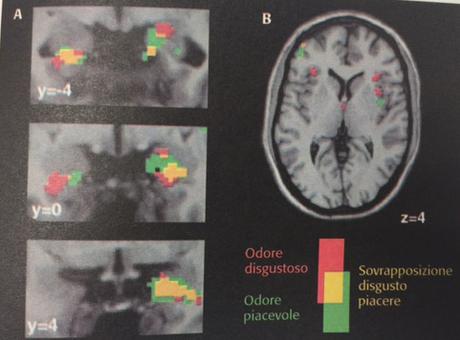

Fue gracias a la tecnología de la resonancia magnetica nuclear funcional como se llego a objetivar la existencia de estas respuestas.

Incluso hay quienes afirman que la simulación de las neuronas espejo no se limitan al plano motor sino que incluye las emociones y las sensaciones de los demás. De hecho, se ha apreciado que algunas zonas del cerebro vinculadas a las emociones se activan lo mismo si somos nosotros quienes las experimentamos que si vemos a otras personas vivenciándolas. Desde esta perspectiva, las neuronas espejo también nos permitirían ser empáticos, ponernos en el lugar del otro y sentir lo que el otro siente. No es casualidad pues que algunos neurocientíficos también las nombren como las " neuronas de la empatía ".